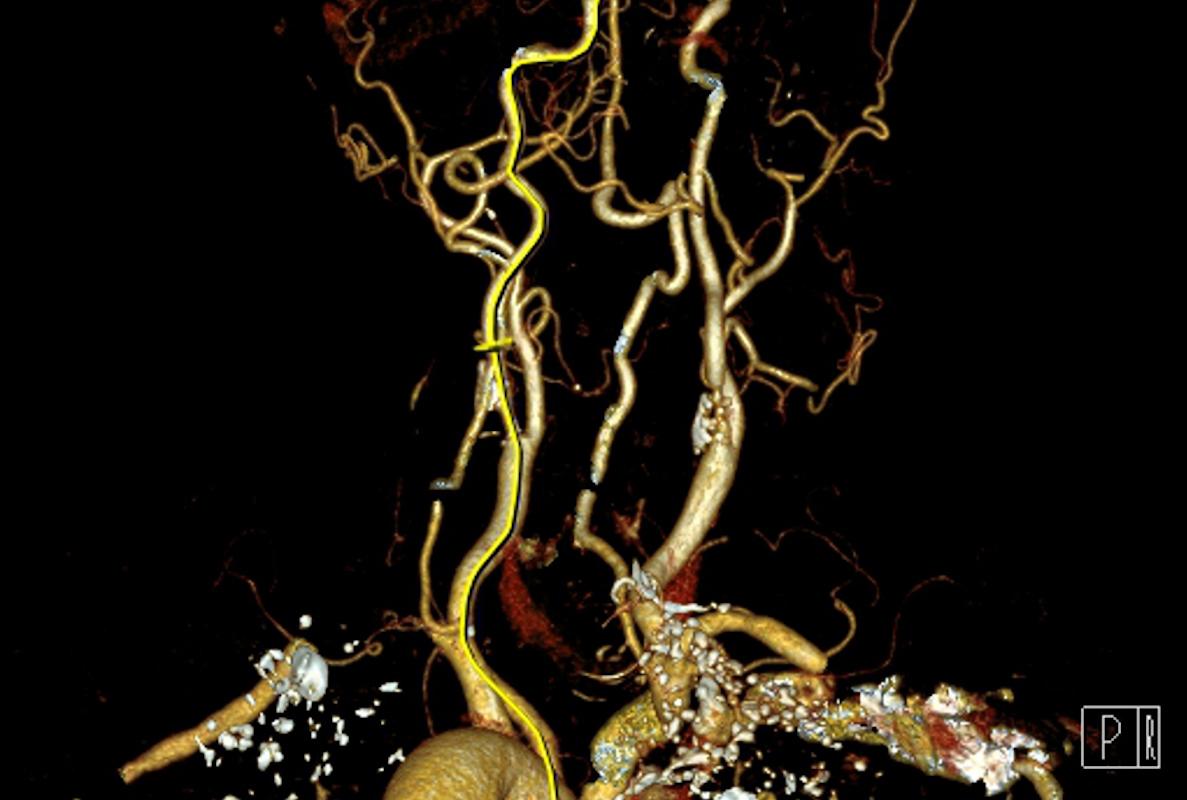

Sur le même mécanisme qu’une dialyse rénale, ce poumon portatif permettra de remplacer l’activité des poumons. « Une petite canule placée dans une veine au niveau du cou ira jusque dans la partie droite du cœur pour faire passer le sang dans la machine afin de l’oxygéner et d’éliminer le dioxyde de carbone. Puis, le sang sera réinjecté dans la partie gauche pour être distribué aux organes », détaille le chirurgien.